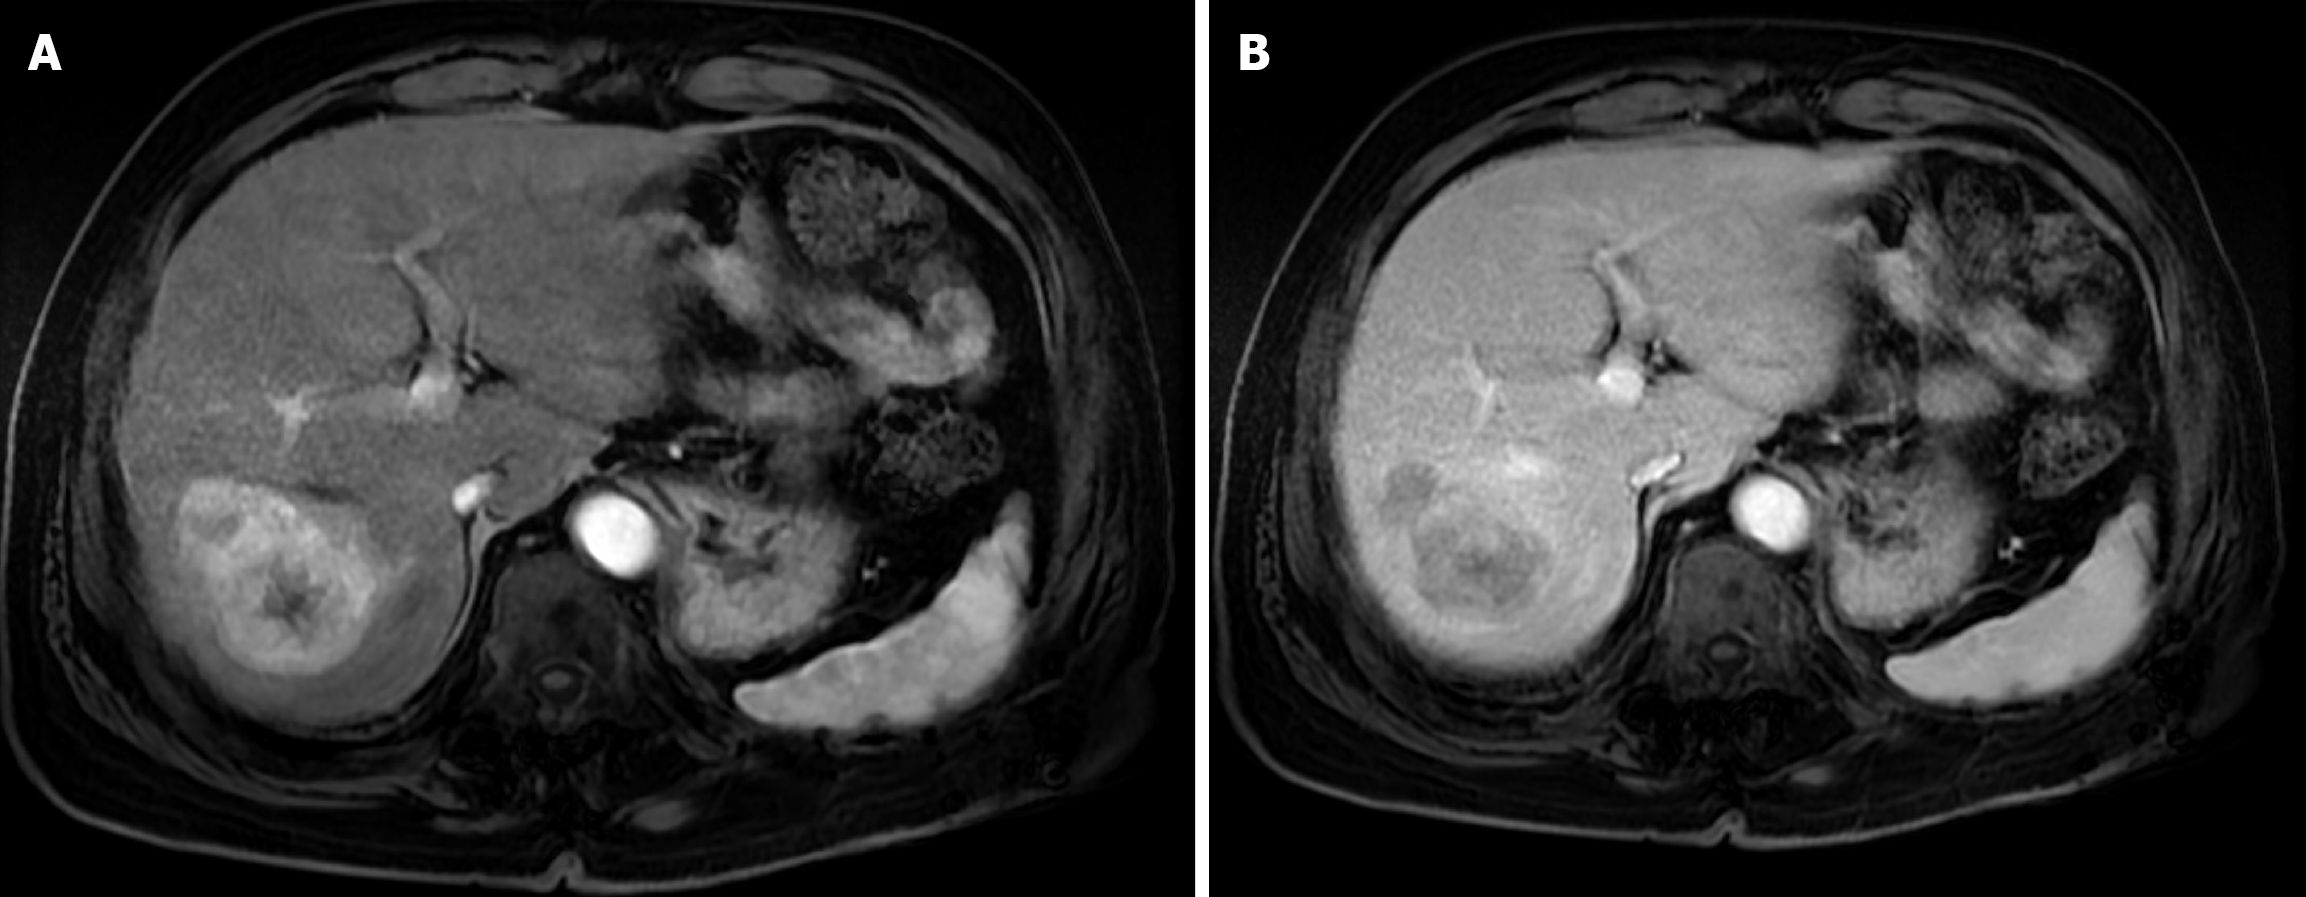

Figure 2 Baseline magnetic resonance imaging of the abdomen.

A: Arterial phase T1-weighted magnetic resonance imaging showed a large, well-defined, arterially enhancing hepatic mass; B: Delayed phase T1-weighted magnetic resonance imaging demonstrated washout of the lesion.